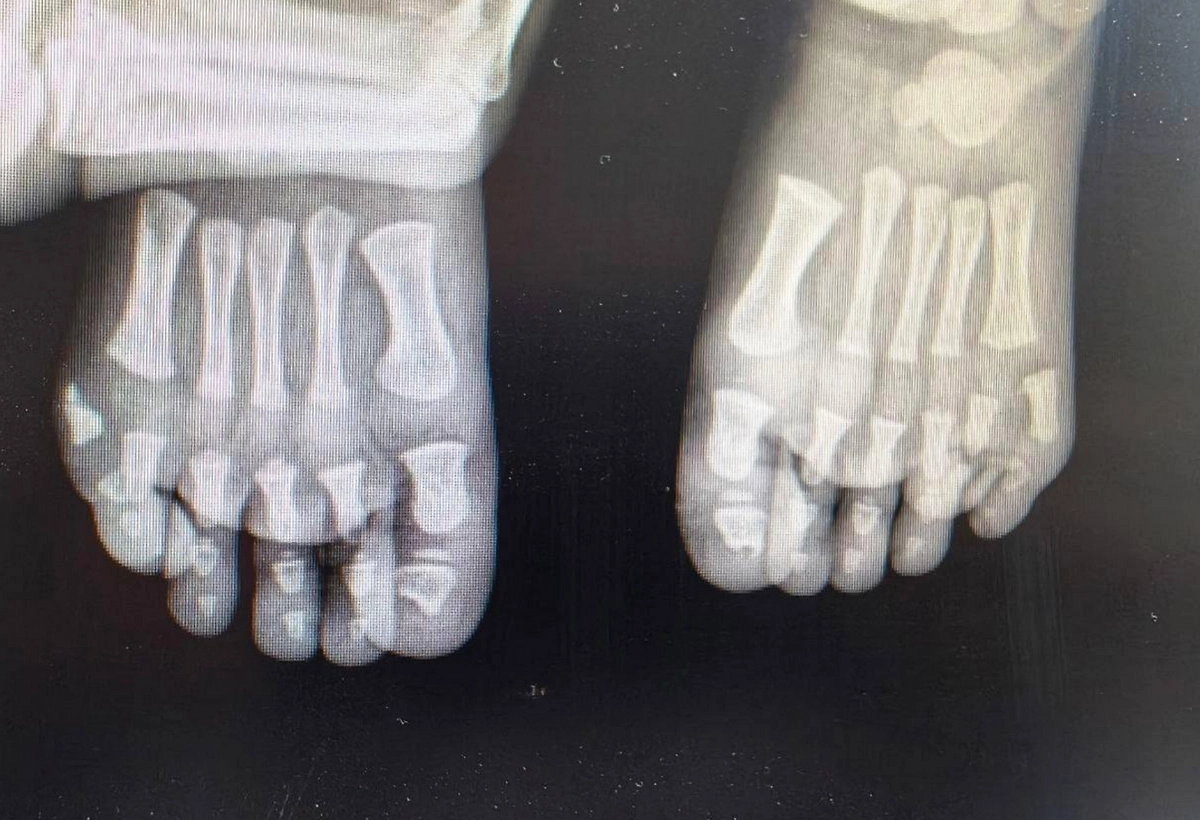

В Московской областной детской клинической травматолого-ортопедической больнице провели операцию мальчику с редкой врождённой особенностью — дополнительными пальцами на обеих стопах.

Ребёнку поставили диагноз полидактилия. Эта патология вызывает не только эстетические сложности, но и физический дискомфорт, в том числе проблемы с подбором обуви. Врачи совместно с родителями приняли решение о поэтапном хирургическом лечении. Уже проведена первая операция — на одной стопе успешно удалён лишний палец.

«Мы восстановили анатомически правильное строение стопы и помогли избежать возможных психологических проблем в будущем», — сообщил главный врач больницы Александр Григорьев.

После завершения реабилитации планируется провести аналогичную операцию на второй стопе. Врачи ожидают, что после лечения ребёнок сможет вернуться к полноценной активной жизни без ограничений.